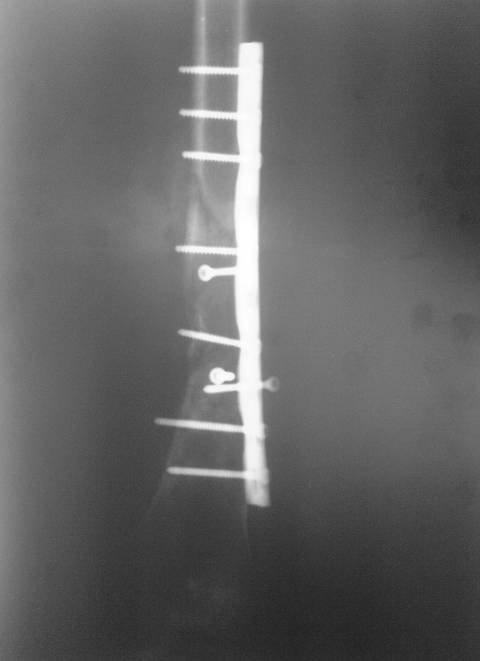

Через 4 месяца стали беспокоить боли и деформация

бедра. На снимке угловая деформация AP - варус 11 град.; lateral - 29

град. Объем движений в коленном суставе: ограничение сгибания до 90

град. Локально - патологическая подвижность в нижней трети бедра.

В мае 2007 года оперирована в Уральском НИИТО г. Екатеринбурга.

Выполнено: полузакрытое удаление пластины и винтов, IM блокируемый

остеосинтез.